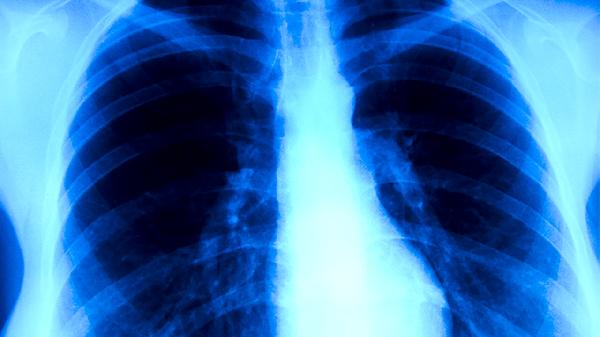

肺结核患者正确佩戴医用外科口罩或N95口罩时,口罩能阻挡含有结核杆菌的飞沫向外扩散。研究显示,规范佩戴口罩可使飞沫传播风险降低较多。患者咳嗽、打喷嚏或大声说话时,口罩能拦截大部分飞沫颗粒。同时健康人佩戴口罩也能减少吸入带菌飞沫的概率,双重防护效果更佳。

当患者口罩未完全遮盖口鼻、佩戴时间过长导致防护性能下降,或口罩出现破损时,飞沫可能通过缝隙扩散。部分结核杆菌可在空气中悬浮较长时间,若健康人未佩戴口罩且在1米内长时间接触,仍存在感染风险。免疫力低下者、儿童等易感人群需特别注意防护。